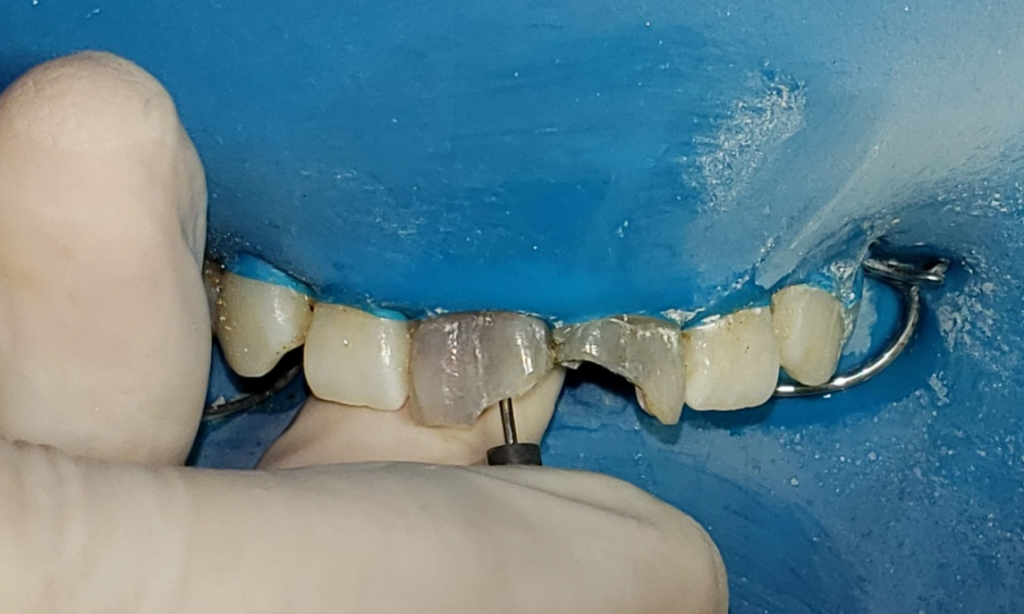

Paciente femenina de 28 años acude a la Facultad de odontología por motivo estético y molestia en el sector anterior y es derivada la asignatura Endodoncia B. Refiere alteración en la coloración de sus incisivos superiores y vergüenza al sonreír y molestia al morder con sus dientes delanteros. Al examen clínico, se observa restauración defectuosa y coronas manchadas (Fig 1-2). La paciente relata una caída hace más de 10 años, tras la cual le realizaron una reparación dental con tornillos metálicos.

Fig. 1 foto inicial Vestibular

Fig. 2 Foto inicial vest y palatina

Fig. 4-5 Eliminacion de composite vista de tornillos

Fig. 5